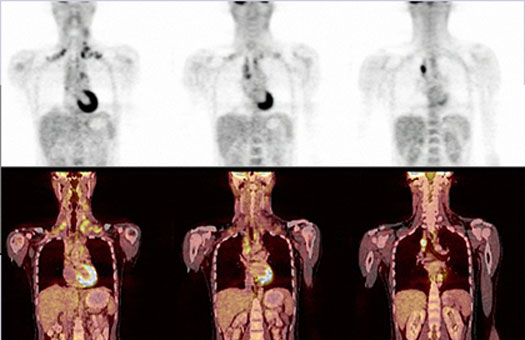

Важную роль стали играть комбинированные систем. Так, ПЭТ системы постепенно вытесняются комбинацией ПЭТ/КТ (Рис.6). Разрабатываются модели ОФЭКТ/КТ, ПЭТ/МРТ. Подобные устройства сочетают в себе все достоинства современных томографических методов.